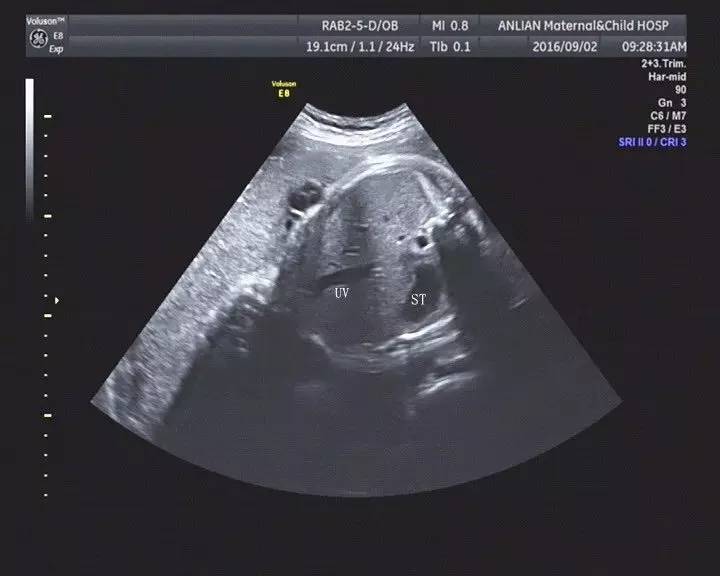

近年,随着产前诊断不断细化、深入,胎儿胆囊作为消化系统的重要组成部分日益受到重视。在孕中晚期超声产前筛查中,偶尔发现胎儿胆囊未见[prenatal non-visualization of fetal gall bladder (PNVGB) ]。当孕妇及家属看到报告单时会恐慌,不安,造成很大心理负担。

造成超声中晚孕期胎儿胆囊未探及的原因分为以下几种:一、孕35周后胎儿胆囊具有明显收缩功能,可能是胆汁排出,胆囊处于收缩状态;二、超声机器的分辨率低、检查医师的经验不足、胎儿的体位不正、肢体遮挡等等,对于过于细小的胆囊结构不能很好的探查和显示;三、发育异常,如囊性纤维化、胆道闭锁、胆囊发育不良等。